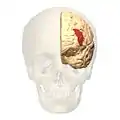

Brodmann area 46, or BA46, is part of the frontal cortex in the human brain. It is between BA10 and BA45.

BA46 is known as middle frontal area 46. In the human brain it occupies approximately the middle third of the middle frontal gyrus and the most rostral portion of the inferior frontal gyrus. Brodmann area 46 roughly corresponds with the dorsolateral prefrontal cortex (DLPFC), although the borders of area 46 are based on cytoarchitecture rather than function. The DLPFC also encompasses part of granular frontal area 9, directly adjacent on the dorsal surface of the cortex.

Cytoarchitecturally, BA46 is bounded dorsally by the granular frontal area 9, rostroventrally by the frontopolar area 10 and caudally by the triangular area 45 (Brodmann-1909). There is some discrepancy between the extent of BA8 (Brodmann-1905) and the same area as described by Walker (1940).[1]